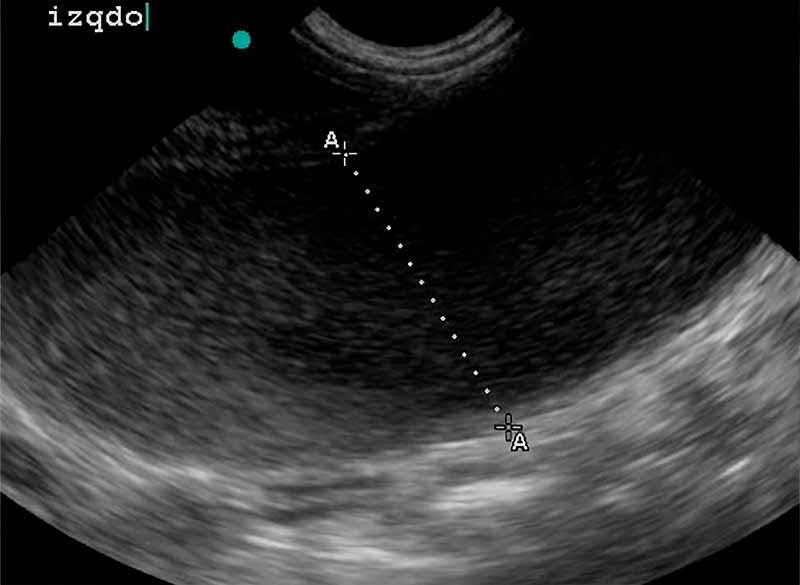

Estudio Ecográfico Especializado:

Se identificó una distensión abdominal marcada con presencia de contenido líquido patológico compatible con proceso uterino.